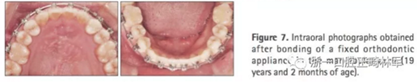

第三階段(圖7,表2)

19歲2月時(shí)行固定矯治排齊下頜牙列建立穩(wěn)定的咬合及正常的覆合覆蓋,持續(xù)1年10月。摘除后(21歲)上下頜用固定保持器,上頜牙弓用Hawley保持器。